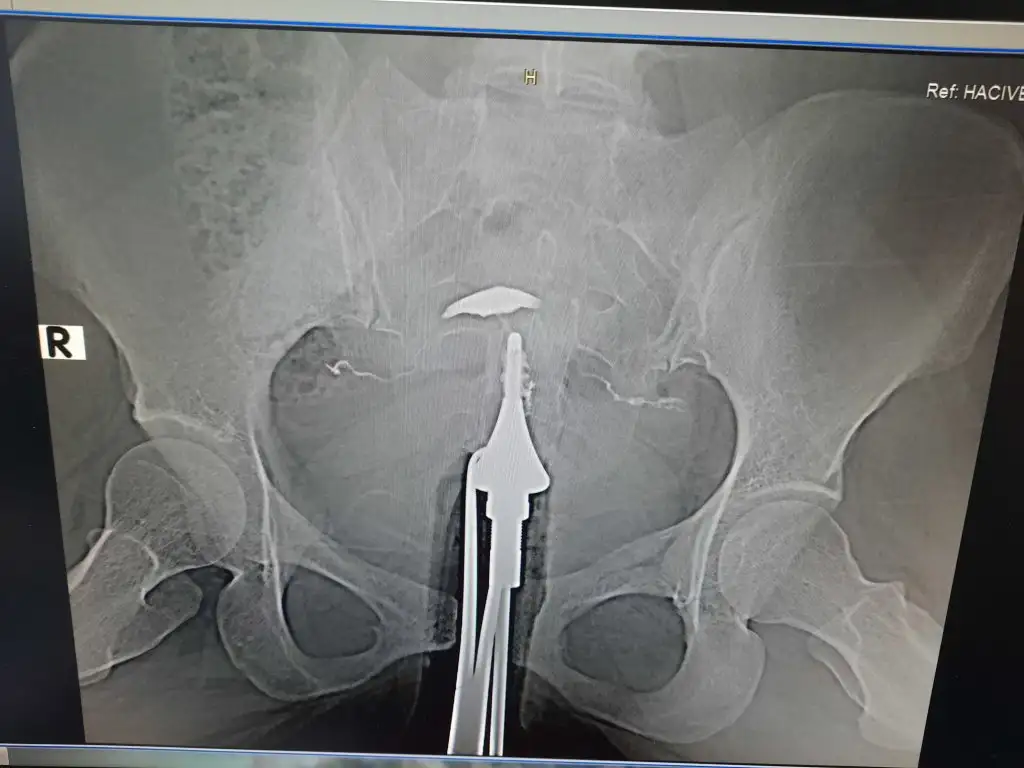

Bu rahim perdeli mi kizlar ben delircem dun doktor bakti güzel dedi benim bugün cd yi alıp bakma şansım oldu resmen rahim yok ortada buna nasıl iyi dedi ?? Perde sonradan oluşur m

Öyle birsey olsa doktor zaten söylerdi kendi kendi stres yapma benceBu rahim perdeli mi kizlar ben delircem dun doktor bakti güzel dedi benim bugün cd yi alıp bakma şansım oldu resmen rahim yok ortada buna nasıl iyi dedi ?? Perde sonradan oluşur mu

Canım sonuç raporu verdiler mi sana? Perde, tıkanıklık, şekil bozukluğu vs o raporda yazması lazımBu rahim perdeli mi kizlar ben delircem dun doktor bakti güzel dedi benim bugün cd yi alıp bakma şansım oldu resmen rahim yok ortada buna nasıl iyi dedi ?? Perde sonradan oluşur mu

Tüpleri gördüm ama rahim net değil pek de anlamam ama sanırım çekimle alakalı perde sonradan oluşmaz doğuştan olan bi şeyBu rahim perdeli mi kizlar ben delircem dun doktor bakti güzel dedi benim bugün cd yi alıp bakma şansım oldu resmen rahim yok ortada buna nasıl iyi dedi ?? Perde sonradan oluşur mu

Öyle birsey olsa doktor zaten söylerdi kendi kendi stres yapma bence

Canım çok iyi bilmiyorum ama perde görüntüsü böyle olmuyor gördüğüm örneklerde. Ama görüntü bana da bir değişik geldi. Tüplerden karın boşluğuna dağıldı mı sıvı? Tek görüntü bu değildir herhalde? Bir de çeken doktordan ziyade radyoloji uzmanı rapor yazmalı asıl o rapor önemli canım var mı elinde?Bu rahim perdeli mi kizlar ben delircem dun doktor bakti güzel dedi benim bugün cd yi alıp bakma şansım oldu resmen rahim yok ortada buna nasıl iyi dedi ?? Perde sonradan oluşur mu